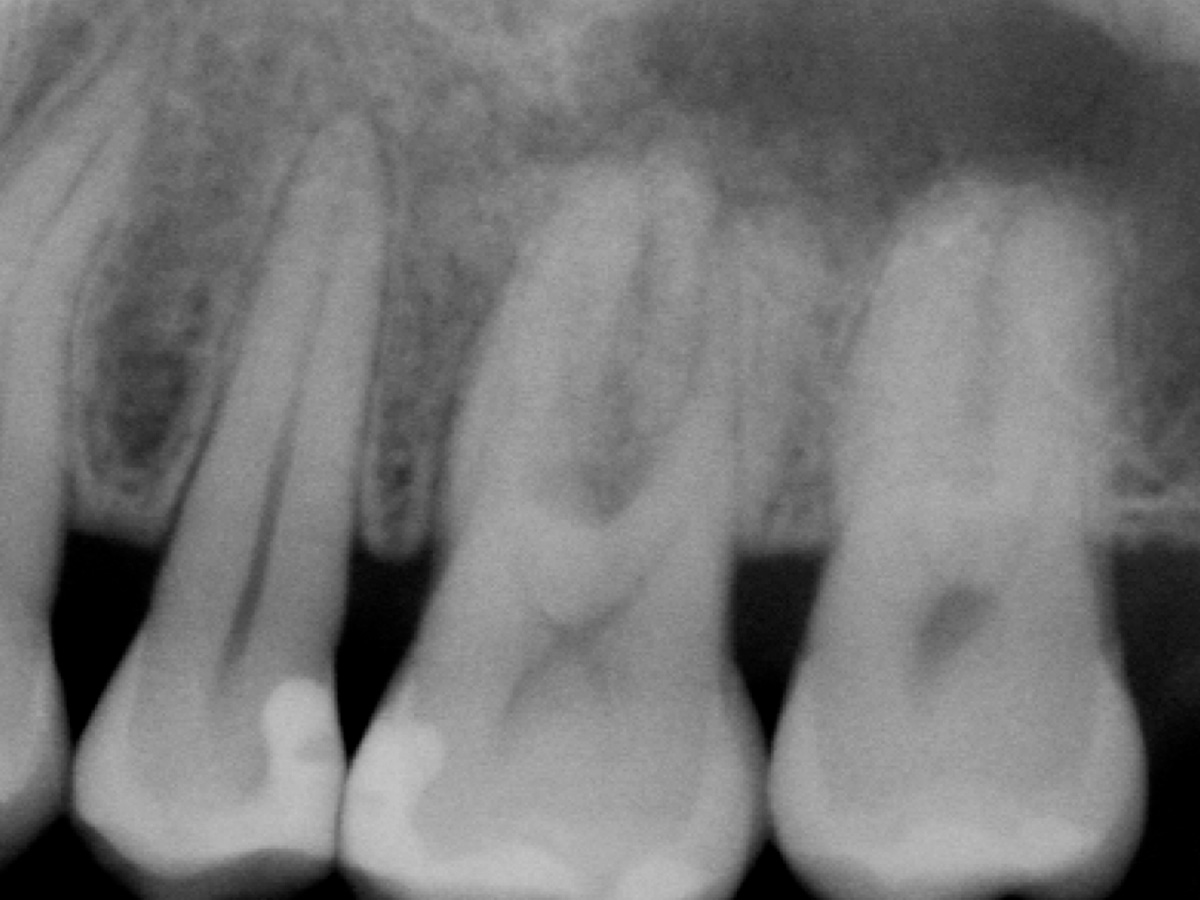

Abbildung 2

Röntgenologische Ausgangssituation Zahn 26: Komplexer parodontaler Knochenabbau im Furkationsbereich sowie periapikal der mesiobukkalen Wurzel.